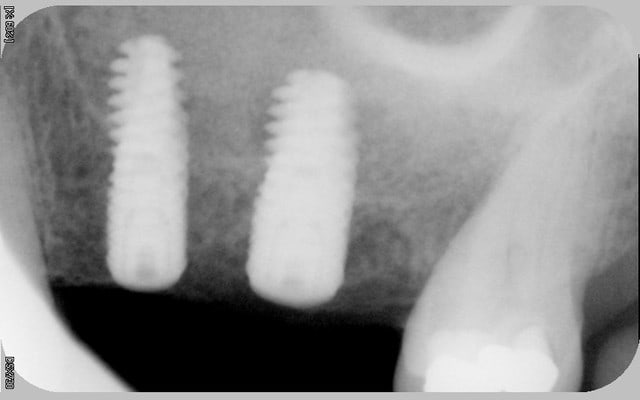

tous mes implants sont ostéo-intégrés, mais je trouve que la cratérisation est très importante et surtout très rapide.

donc pour moi, il y a un problème même si le taux de succès est de 100% en 2 ans.

mais dans 10 ans?

voici les radios le jour de la pose

le krestal doit être en crestal et non en infra-osseux: il s'agit d'une connectique à plat et non d'un cône morse.